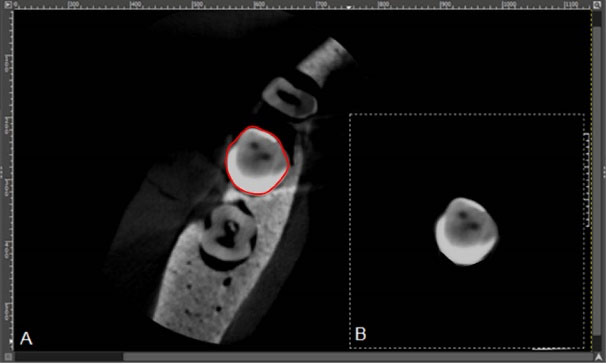

and illustrate CBCT and micro-CT images obtained from teeth restored with metal-ceramic and all-ceramic crowns.

Figure 5.

The micro-CT images: A. All-ceramic crown without a gap. B. All-ceramic crown with a gap of 0.3 mm. C. All-ceramic crown with a gap of 0.5 mm. D. Metal-ceramic crown without a gap. E. Metal-ceramic crown with a gap of 0.3 mm. F. Metal-ceramic crown with a gap of 0.5 mm